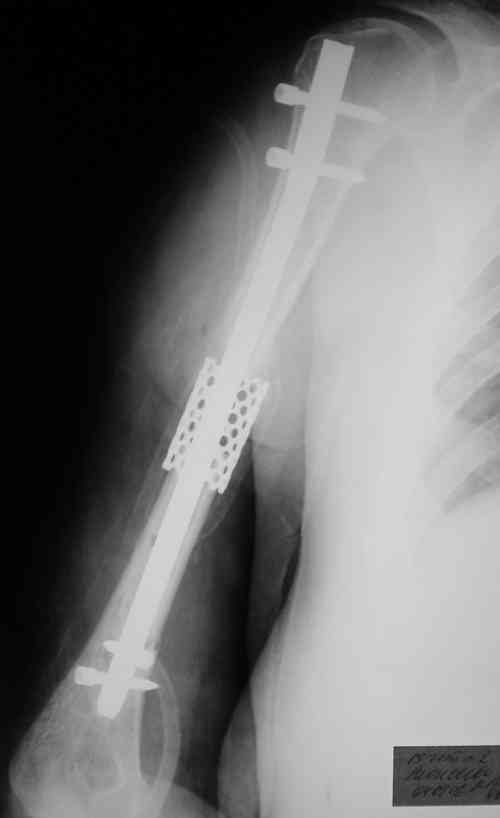

Такие надмыщелковые переломы в изолированном виде у нас в последние годы обычно фиксируются плоским титановым стержнем a la Зверев-Ключевский антеградно. Но тут еще и вышележащие проблемы.

Наверно, можно пойти на укорочение, убрав металлический цилиндр, не такой уж большой дефект. Снимки в чем-то похожего пациента прилагаю - тоже несращение диафиза после многократных операций, и надмыщелковый свежий перелом (случился после удаления обломка стержня аппарата).